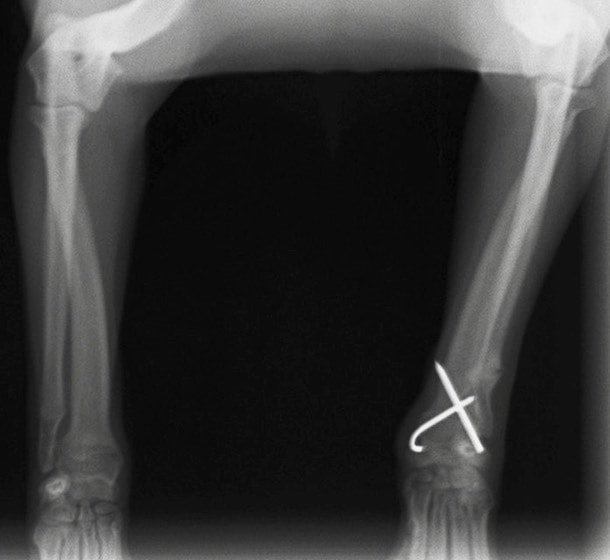

症例3:キルシュナーワイヤーのピンニングによる整復

ペルシャ猫 11ヶ月齢 雄

他院にて左大腿骨遠位の成長板骨折(salter-harrisⅠ型)が認められており、治療相談を目的として来院。当院にて、キルシュナーワイヤーを用いたピンニングにより骨折部位の整復を行いました。術後の経過は良好で、現在も経過観察中です。

術前レントゲン

術後レントゲン